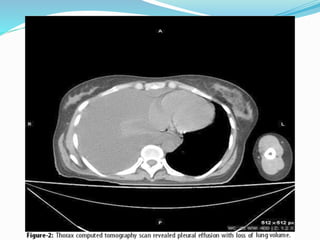

Pleural effusion with complete

right lower lobe collapse

This is a chest x ray taken from a 48y male

Who presented with left sided chest pain

Dry cough and wt loss since 4 month.

Chest x ray showed a left opaque

Thorax with mediastinal shift opposite to

Opacified side,

These findings was suggestive of a massive

Pleural effusion on clinico-radiological

Assessment.

However thoracocentesis revealed dry tap

On ultrasound of the chest disclosed a

solid, smooth marginated mass

occupying the left hemithorax with

multiple well-defined

rounded cystic spaces and focal areas of

calcification. There was no pleural effusion.

Computed tomography (CT) of the thorax showed

a well-defined heterogeneously enhancing mass

measuring 16.6cm x 13.7cm, and occupying almost

the whole of the left hemi thorax. The mass showed

non-enhancing areas with CT values of 40±5 HU

suggesting a cystic degeneration and areas of

calcification. The mass displaced the mediastinum to

the right side with preservation of the fat planes

between the mediastinum and the mass.

Bipopsy confirmed the case as giant primary pulmonary

fibrosarcoma.